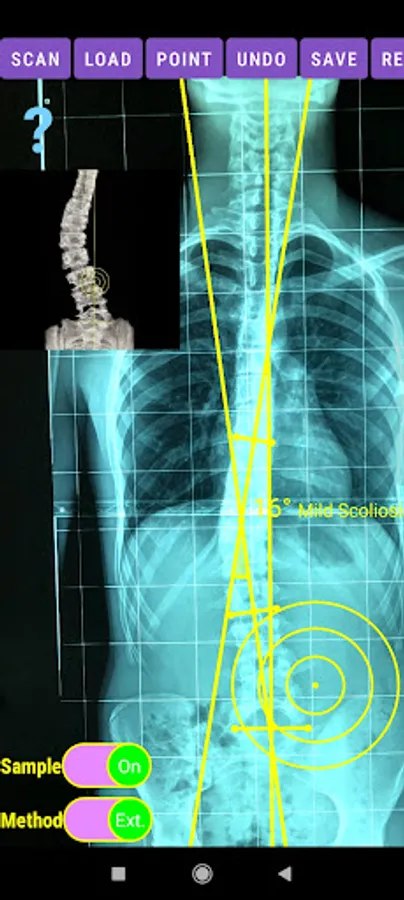

The app offers a very convenient way to asses spinal deformity by measuring the Cobb angle. The first thing is to load one image from your photo library or capture a photo from x-rays photos of a patient. The app offers two measuring methods, the simple (Sim.) and the extended (Ext.). By clicking the relevant option, the option is highlighted and the respective method is activated.

-Offers a very convenient way to determine the most accurate possibly way at once. By marking four points at the same X-ray, at each spine the App calculates the Cobb angle. In cases where values are out of normal ranges, the scoliosis is categorized according to measured angle as mild, moderate, severe. To simplify the process and to minimize inter-observer errors usually by not selecting the actual end vertebra, the app offers also in ext mode the ability to draw the vertical reference line through the patient’s sacrum and to identify more easily the end vertebrae (ext method).